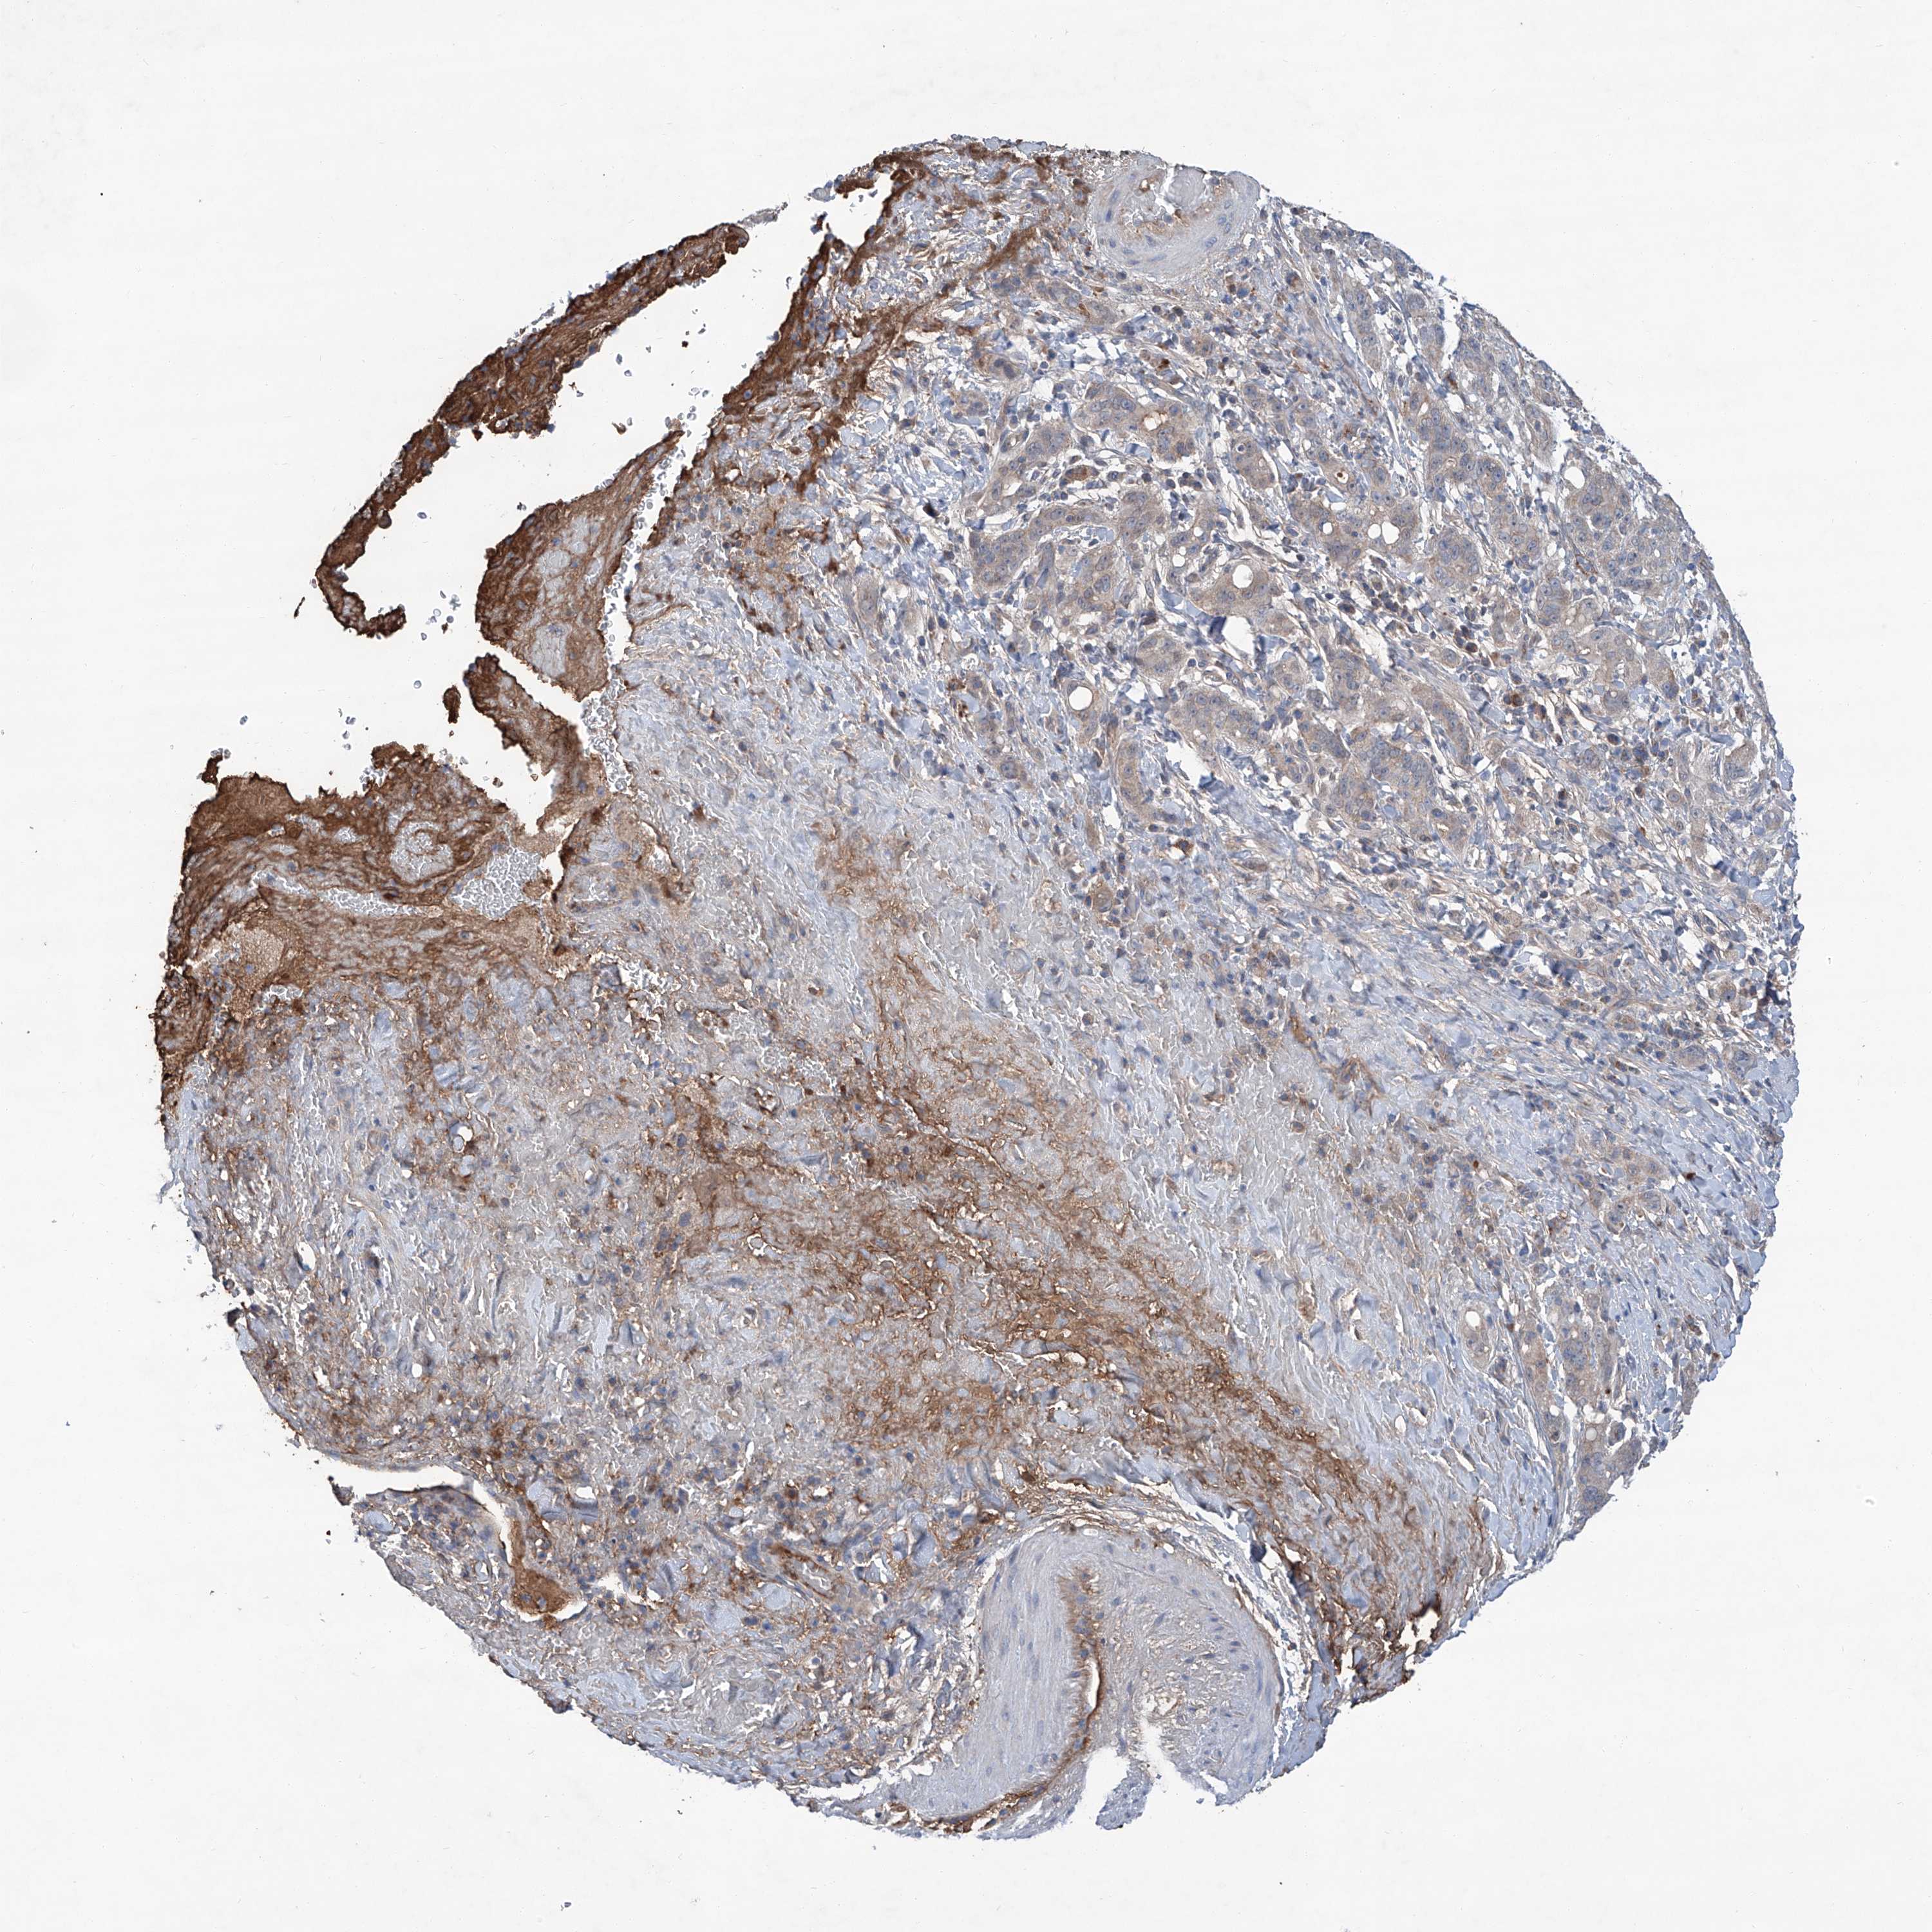

LIVER CANCER - Protein expressioni

A mouse-over function shows sample information and annotation data. Click on an image to view it in a full screen mode. Samples can be filtered based on level of antibody staining by selecting one or several of the following categories: high, medium, low and not detected. The assay and annotation is described here.

Note that samples used for immunohistochemistry by the Human Protein Atlas do not correspond to samples in the TCGA dataset.

Antibody stainingi

Antibody staining in the annotated cell types in the current human tissue is reported as not detected, low, medium, or high, based on conventional immunohistochemistry profiling in selected tissues. This score is based on the combination of the staining intensity and fraction of stained cells.

Each image is clickable and will lead to virtual microscopy that enables deeper exploration of all samples and also displays staining intensity scores, fraction scores and subcellular localization as well as patient and tissue information for each sample.

Antibody HPA031794

Staining

High

Medium

Low

Not detected

Intensity

Strong

Moderate

Weak

Negative

Quantity

>75%

75%-25%

<25%

None

Location

Nuclear

Cytoplasmic/membranous

Cytoplasmic/membranous,nuclear

Cholangiocarcinoma

Carcinoma, Hepatocellular, NOS